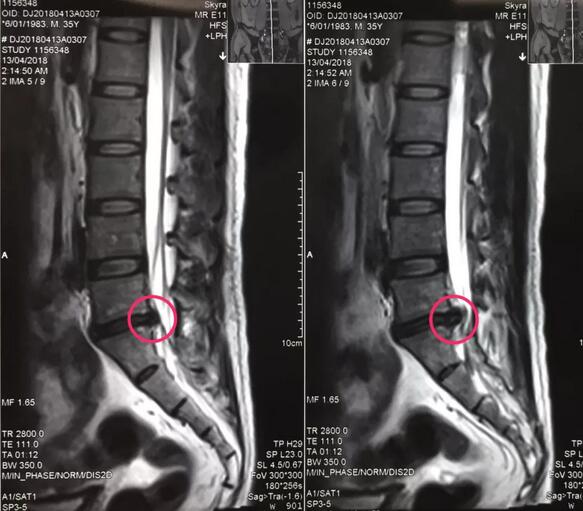

八零后李先生来自山西长治,是家里的顶梁柱,半年前开始出现腰痛不适,工作繁忙没有时间看病,后来突然加重并出现左下肢放射样抽痛,走路都走不了,在当地多家医院检查确诊为腰椎间盘突出症,治疗方案都是开刀手术,打钉固定,小李拒绝开放手术,回家卧床四个多月,仍然不能下地走路,亲朋友好友四处寻医问药,终于从病友群里打听到,按摩视频 可以微创手术,效果很好,就专程前来。骨一科专家团队给李先生进行了详细的查体和认真的读片,告诉李先生诊断确实是腰椎间盘突出症,适合孔镜微创,不用开放手术,不用打钉固定,李先生欣然接受。7月27日,骨一科微创团队为李先生实施了经皮椎间孔镜下髓核摘除术,手术一小时,术后下肢抽痛症状完全解除,终于可以下地走路了,李先生和家人对手术效果非常满意。

骨一科专家团队介绍,随着生活节奏的加快和生活方式的改变,越来越多的年轻人也得了腰椎间盘突出症,腰椎间盘突出症不可怕,开大刀手术的时代已经过去,骨科已经进入了孔镜微创时代,我们可以根据患者情况做到日间手术(当日住院、当日手术、当日出院),1cm的小口就可以取出椎间盘,不打钉子花费少,不用久卧康复快。中心医院骨一科团队希望能用最小的创伤为更多的患者解除腰腿之痛。